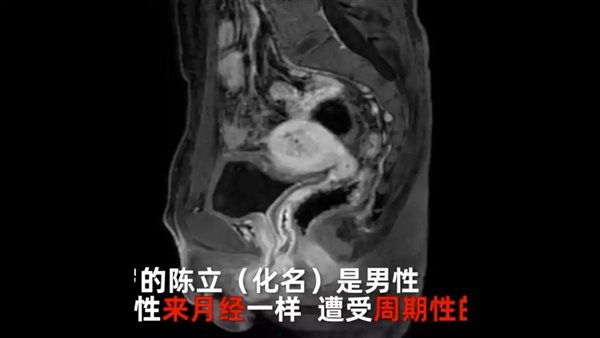

وقال الرجل إنه خلال فحص طبي العام الماضي، وجد أنني لدي كروموسومات جنسية أنثوية، حيث كشفت الفحوصات الطبية الإضافية أن لدي أعضاء تناسلية بما في ذلك الرحم والمبايض، وكانت مستوياته من هرمون الذكورة هرمون الأندروجين أقل من المتوسط ، في حين أن مستويات الهرمونات الجنسية الأنثوية ونشاط المبيض كانت مماثلة لتلك الموجودة لدى النساء البالغات الأصحاء.

وذكر الأطباء أن الرجل كان يحيض بانتظام مثل المرأة لمدة 20 عامً، وتوصلوا في النهاية إلى استنتاج مفاده، أن لديه ثنائية الجنس، بأعضاء تناسلية من الذكور والإناث، وهذا يعني أن الدم في بوله وألم في بطنه سببه الحيض.